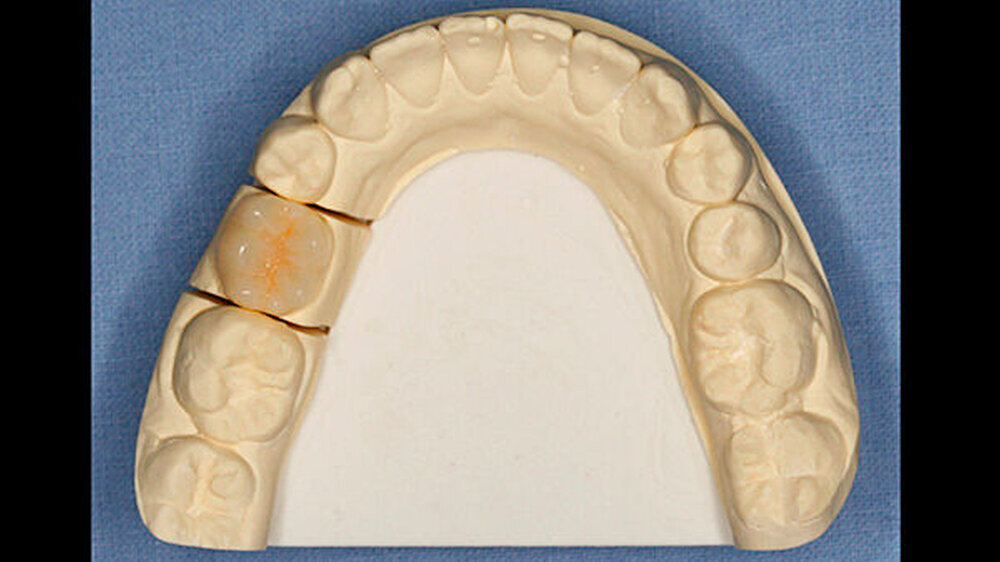

Da die junge Patientin bisher keine Restaurationen benötigt hatte, sprach sie sich vehement für eine möglichst wenig oder sogar non-invasive Vorgehensweise aus. Weil der Zahn 75 prinzipiell völlig intakt war, sich nur eben im Vergleich zu den benachbarten permanenten Zähnen in Infraokklusion befand, war das primäre Ziel der Restauration, diesen in maximale Interkuspidation zu bringen. Deshalb wurde vereinbart, die bis zur Interkuspidation fehlende Zahnhartsubstanz - etwa ein Drittel der klinisch sichtbaren Krone - durch ein Onlay auszugleichen. Diese Lösung entsprach zusätzlich dem Wunsch der Patientin, nach Möglichkeit eine non-invasive Behandlung zu erhalten.

Unmittelbar nach der Entbänderung erfolgte deshalb die Abformung beider Kiefer (Aquasil Ultra Heavy und Aquasil Ultra LV, Dentsply DeTrey) sowie eine Bissnahme im Schlussbiss (Futar Fast (1:1), Kettenbach GmbH). Im Labor erfolgte die Herstellung eines Overlays aus Komposit (SR Adoro, Ivoclar Vivadent) (Abbildungen 4 bis 6), das etwa zehn Tage nach der Abformung eingesetzt wurde.